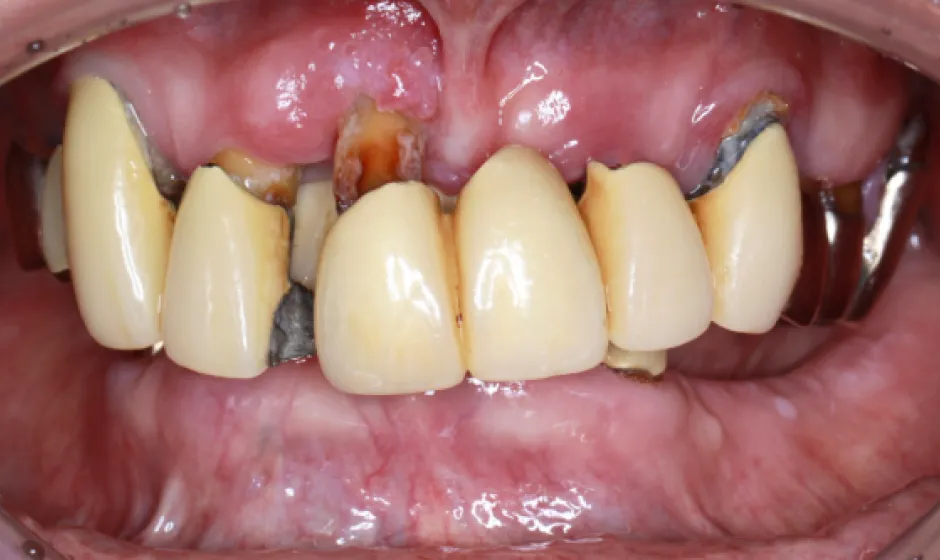

03歯がボロボロの方への

全顎治療むし歯や歯周病が広がり、「どこから治せばいいのか分からない」状態は、痛みだけでなく食事や会話、見た目のストレスにもつながります。大杉歯科医院では、まず精密に検査し、残せる歯・治療が必要な歯を見極めたうえで、治療の優先順位を整理します。仮歯で噛み合わせを整えながら、補綴やインプラントなどの選択肢を組み合わせ、機能と審美の両立を目指します。

いきなり理想を押しつけるのではなく、現実的に続けられる計画で、お口全体を立て直す治療をご提案します。症例1

症例2

- 治療名

- 重度虫歯からの全顎インプラント治療

- 患者様

- 40代男性

- 執刀医

- Dr. 大杉

- 治療期間

- 1年

- 治療費

- 上顎:3,630,000円(税込)

下顎:3,630,000円(税込) - リスク

- 術後、硬い物を食べないでください。

インプラントが骨に結合するまで2ヶ月かかります。

この期間中に強い負荷をかけると、結合しないことがあります。